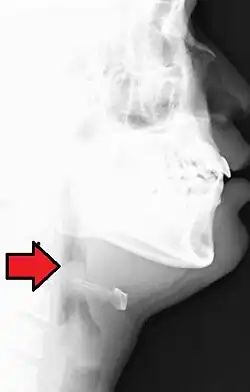

A epiglotite é uma infecção bacteriana de evolução rápida dos tecidos supraglótidos que provoca a obstrução, por vezes fatal, das vias respiratórias. É uma emergência médica. Em 95% dos casos, o germe responsável é o Haemophilus influenzae.[1]

O começo geralmente brusco de dificuldades respiratórias numa criança com 3-6 anos de idade, com progressão rápida (em horas), associado a disfagia, febre, estado tóxico, estridor respiratório, que progride para obstrução das vias aéreas, cianose, prostração e choque, compõem o quadro clínico desta infecção. Baba em excesso, cianose (pele de coloração azulada), dor de garganta, febre, calafrios, tremores, entre outros sintomas. Geralmente transmitida por via respiratória, pode rapidamente causar complicações respiratórias, apesar de atingir a glote e a epiglote, aparelhos do sistema digestório responsáveis pelo isolamento do bolo alimentar das vias respiratórias.[2]

O diagnóstico deverá ser rápido, mas o primeiro passo para o tratamento deverá ser a manutenção da permeabilidade das vias respiratórias: de eleição é a entubação endotraqueal e, se não for possível uma traqueotomia. Ao mesmo tempo deve administrar-se antibióticos. Este tipo de patologia exige uma permanente unidade de cuidados intensivos (UCI).